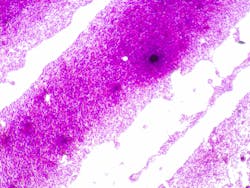

An April 17 retrospective cohort study published in the journal BMC Infectious Diseases entitled, “Clinical burden of Acinetobacter baumannii, including carbapenem-resistant A. baumannii, in hospitalized adult patients in the USA between 2018 and 2022” aimed to address the limited epidemiological data available on Acinetobacter baumannii and carbapenem-resistant A. baumannii (CRAB) in U.S. hospitals. Researchers analyzed microbiology data from the PINC AI Database, covering hospitalized patients across the U.S. from January 1, 2018, to December 31, 2022. The goal was to determine the incidence rates of A. baumannii and CRAB at both hospitalization and individual patient levels, as well as to assess patient characteristics, comorbidities, and clinical outcomes associated with these infections.